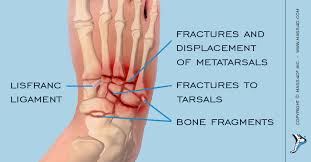

Lisfranc Injury : Lisfranc Midfoot Injury Orthoinfo Aaos. Wherever you are in your recovery, this is a place to share our stories, pics. A lisfranc joint injury happens when you damage bones or connective tissue called ligaments in the middle part of your foot. What is a lisfranc injury? A lisfranc injury is a tarsometatarsal fracture dislocation characterized by traumatic disruption between the articulation of the medial cuneiform and base of the second metatarsal. A lisfranc injury or lisfranc sprain is an injury to the ligaments in the middle part of the foot, called the midfoot.

It is possible to sprain the lisfranc ligament, which does not require surgical intervention. A lisfranc injury, also known as a lisfranc fracture, happens when bones break or ligaments tear in the region in the middle of the feet. Sometimes, the injury is a simple dislocation (ligament injury), and sometimes a broken bone occurs. Partial ligament tears with no instability normal lisfranc. A lisfranc injury or lisfranc sprain is an injury to the ligaments in the middle part of the foot, called the midfoot.

Radiologists must have a thorough understanding of anatomy, mechanisms, and patterns of these injuries to diagnose and help. A lisfranc injury, also known as a lisfranc fracture, happens when bones break or ligaments tear in the region in the middle of the feet. A lisfranc injury occurs when one or more of the metatarsal bones are displaced from the tarsus, which is a cluster of bones at the top of the foot, just below the ankle joint. However, most athletes are able to successfully. Stable lisfranc injuries that do not require surgery may cause an athlete to miss 2 months or more of their season. Lisfranc injuries are a spectrum of injuries to the tarsometatarsal joint complex of the midfoot. Lisfranc injury or midfoot injury that result if bones in the midfoot are broken or ligaments that support the midfoot are torn. • medial edge of 2nd mt base should line up with the medial edge of middle cuneiform. A lisfranc injury or lisfranc sprain is an injury to the ligaments in the middle part of the foot, called the midfoot. Lisfranc injury indicates disruption between. Recovery can be slow and painful. It can occur in one or both feet. Ebraheim's animated educational video describing lisfranc injury.